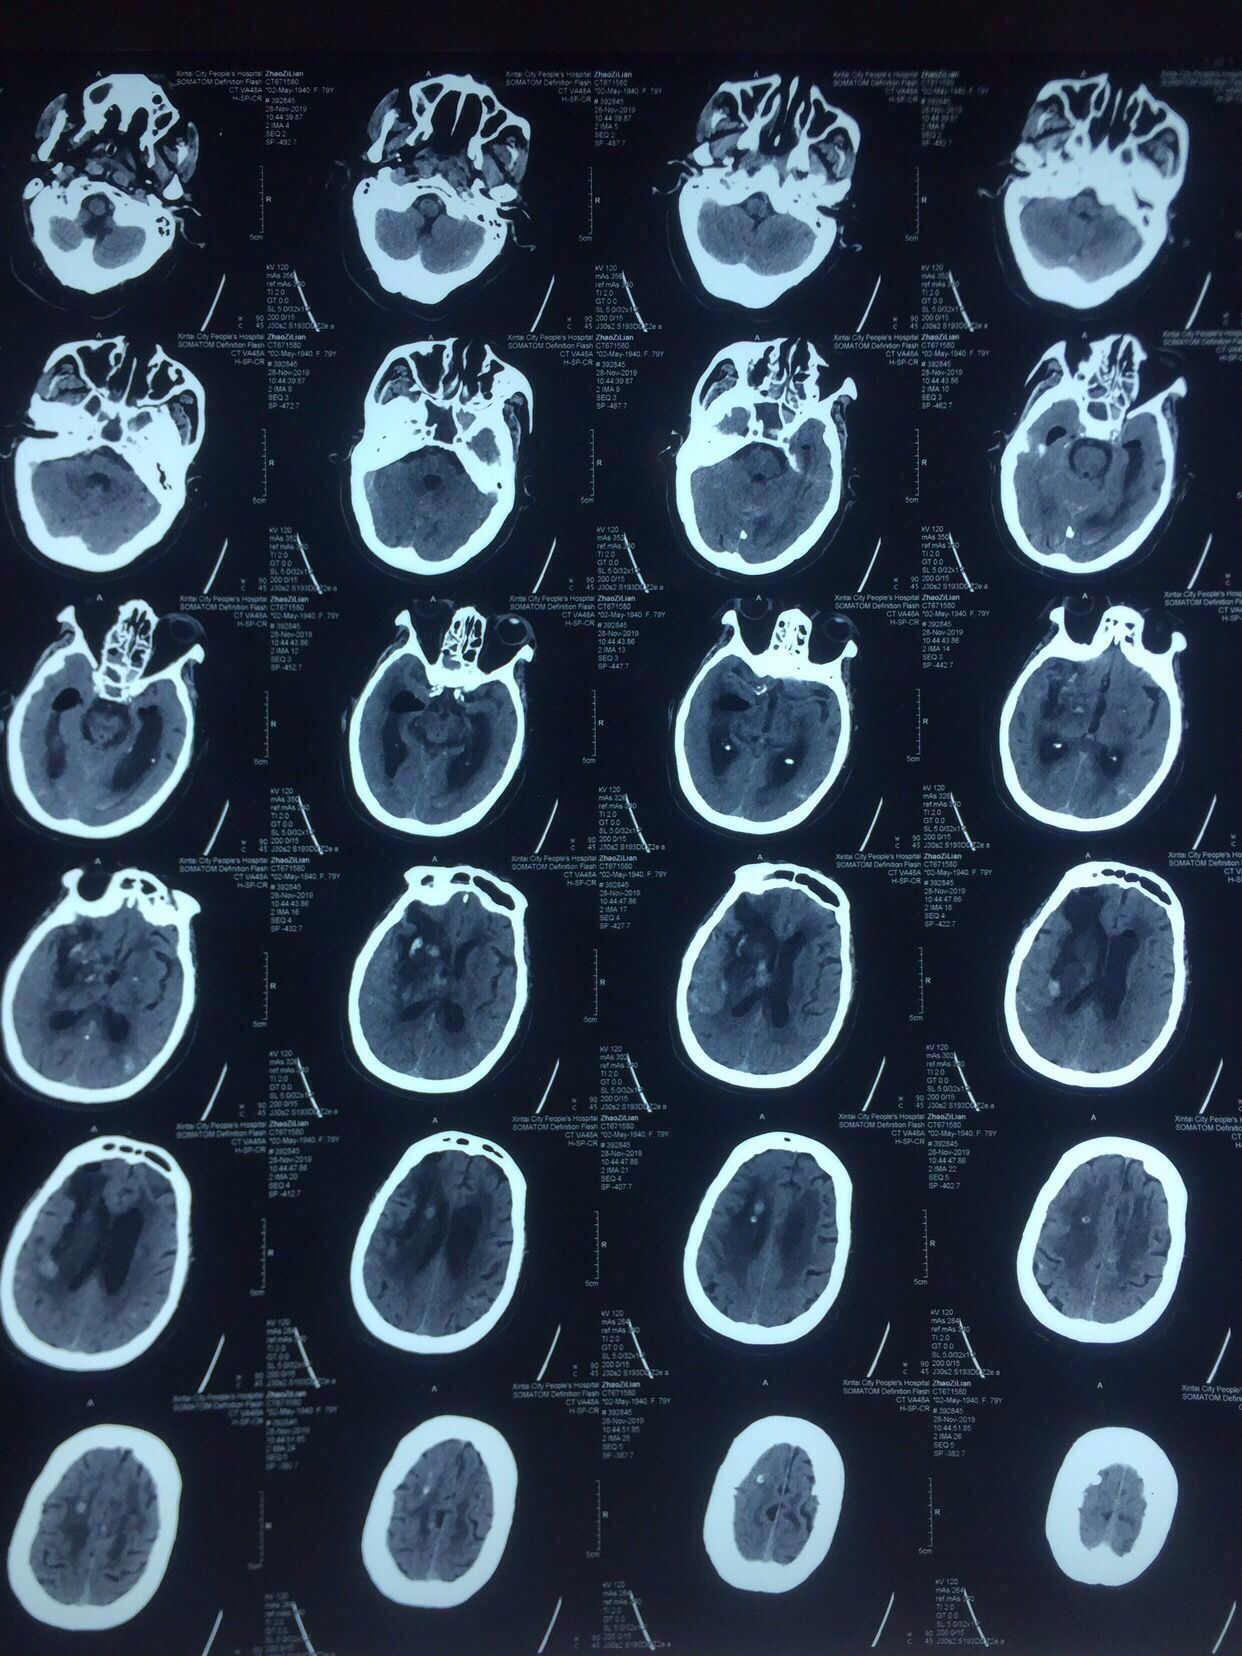

次日复查如上图:

出血未再增大。

术后第7天复查,见上图,血肿引流比较充分。